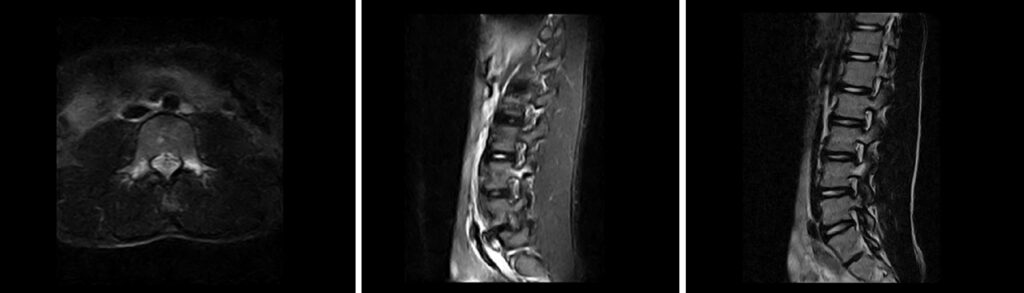

実際の症例を見せていただけますか。

例えばこれは、3週間前から腰部痛と違和感がある15歳男性のケースです。既往歴・手術歴はなく、初診時のレントゲン撮影ではアライメント良好で異常もなかったのですが、その後も症状が続いたため、疲労骨折を疑い、後日あらためてS-scanで腰椎MRI検査を施行しました。その結果、L4横突起両側にT2高輝度・STIR高輝度が認められたため、第4腰椎分離症と診断しました。

小学校高学年以降になると、腰椎分離症で来院する方は多いですね。近年は体が硬い子が多いのか、事前に適切なストレッチをせずにスポーツをすると腰痛が出て受診してきます。基本的にこの年代では腰痛は出ないため、結構な確率で分離症の診断が得られます。